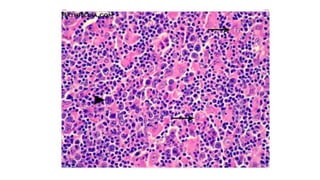

VI THỂ

- Cấu trúc nổi trội: dạng nang hay dạng lan tỏa

- Loại tế bào chiếm ưu thế: tế bào nhỏ, tế bào lớn, hỗn hợp tế bào lớn và

tế bào nhỏ, nguyên bào miễn dịch, nguyên bào lympho

- Thường không thấy đặc điểm đa hình thái tế bào

ULPA, nang, ưu thế tế bào nhỏ nhân khía (WF2)

ULPA, lan toả, hỗn hợp tế bào lớn và tế bào nhỏ(WF6)

ULPA, lan toả, tế bào lớn (WF7)

ULPA, tế bào lớn,nguyên bào miễn dịch (WF8)

ULPA, nguyên bào lympho (WF9)

VI THỂ - Cấutrúc nổi trội: dạng nang hay dạng lan tỏa - Loại tế bào chiếm ưu thế: tế bào nhỏ, tế bào lớn, hỗn hợp tế bào lớn và tế bào nhỏ, nguyên bào miễn dịch, nguyên bào lympho - Thường không thấy đặc điểm đa hình thái tế bào